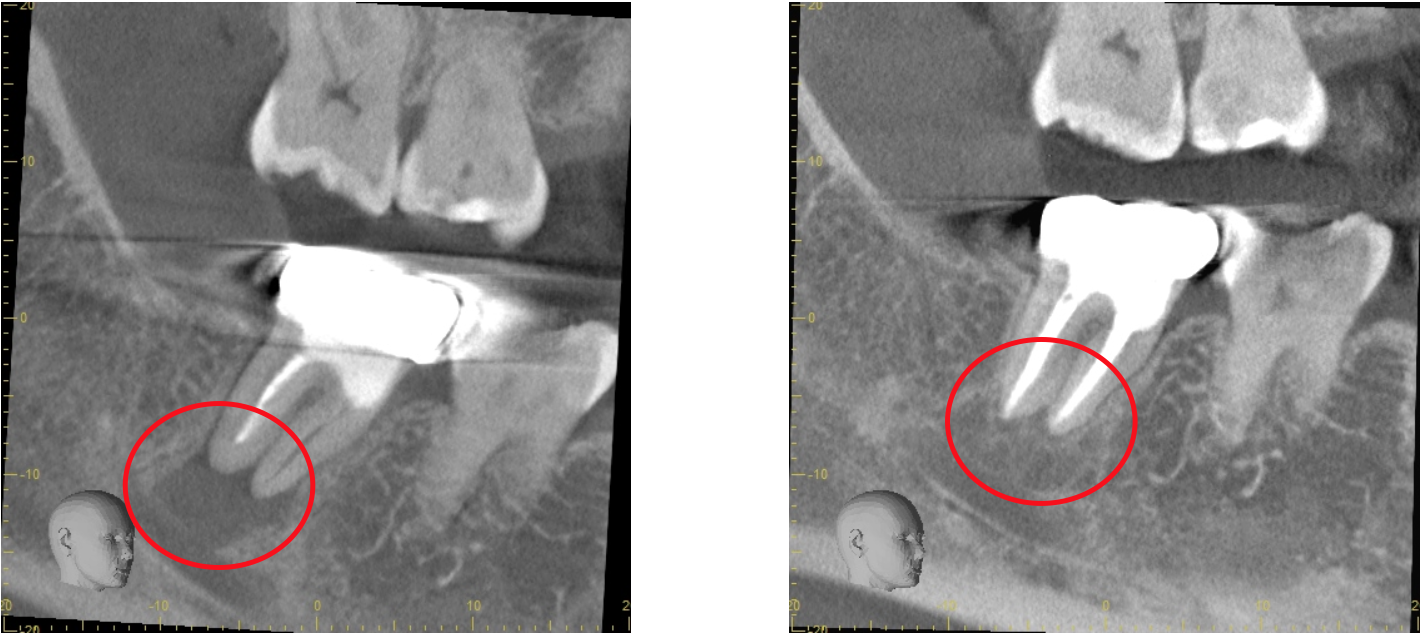

通常の根管治療を行っても症状が良くならない場合には外科的根管治療が必要となってきます。

歯根の外側に感染が及んでいる場合、通常の根管治療では感染源を除去することができないため、感染部位周辺の歯肉から感染源に直接アプローチする必要があります。

感染部周辺の歯肉を切開し、歯根の先端の病変部分を露わにします。

歯槽骨に穴を開け歯の根本から根管治療を行い、感染源を除去します

感染源を除去した後、感染している歯根の先端も取り除きます。

詰物をして歯槽骨の回復を待ち、切開部を縫合して完了です。